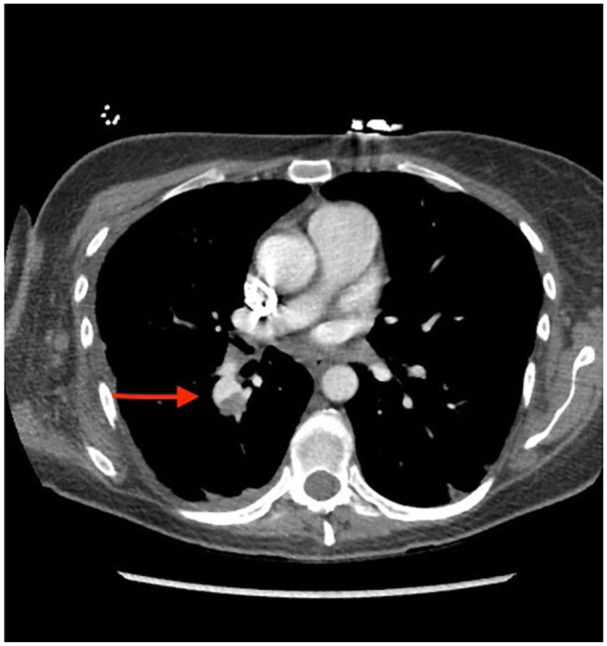

Pulmonary artery pseudoaneurysms (PAPAs) are rare and potentially fatal vascular complications that often require early detection. Most common etiologies are infection and trauma (including iatrogenic from procedures like pulmonary artery catheterization or lung biopsy). Early clinical signs include hemoptysis, dyspnea, and hemodynamic instability. Diagnostic workup should always include appropriate imaging modality, with computerized tomography (CT) and CT angiography as important diagnostic tools. Given the limited number of reported cases, treatment is not definitive and is largely guided by symptoms and patient present. In the case of massive hemoptysis, coil embolization or pulmonary vascular stenting is the preferred option. In the current case of asymptomatic PAPA, we will outline a more conservative approach to treating PAPA.